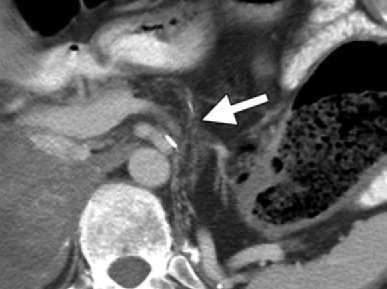

Pancreatic atrophy is a natural consequence of aging, and by the time a person is 85 years old, their pancreatic weight can often drop from the typical range of 60–100 grams to 40 grams or less. This can make it easier to detect a small or mild pancreatic tumor, which can often appear more apparent on imaging examinations in comparison to the atrophied gland.

The damage to the pancreas is irreversible, but with adequate treatment, the patient can control a number of the symptoms. Medication, endoscopic procedures, or surgery are all possible forms of pancreatitis treatment. Type 3c diabetes develops in approximately one-third of those with chronic pancreatitis. This develops when pancreatic injury renders the organ incapable of secreting insulin. Chronic pancreatitis patients can sometimes develop fluid-filled sacs on the pancreas’s surface (pseudocysts). Chronic pancreatitis has a mortality rate that is higher than that of the general population; nonetheless, the 10-year survival rate following diagnosis is believed to be between 69 and 80 percent.